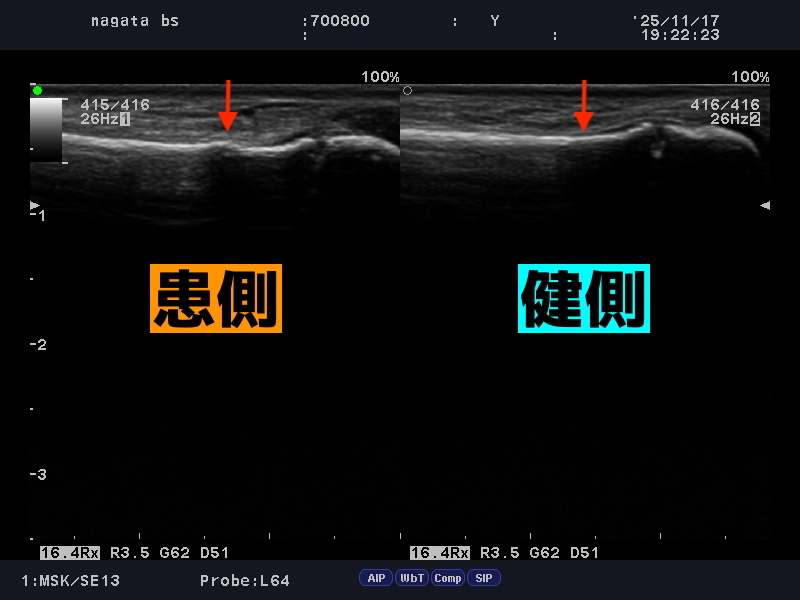

エコーの精度の高さ

患側の骨に不整像が確認できます

念の為エコーでも観察してみると、骨の不整像を確認いたしました。

外力としては大きくはなかったようですが、小児の特徴的な骨折である、「若木骨折」でした。

若木骨折はレントゲンだと、左右を比較しないと見逃してしまうこともあるようで注意が必要です。